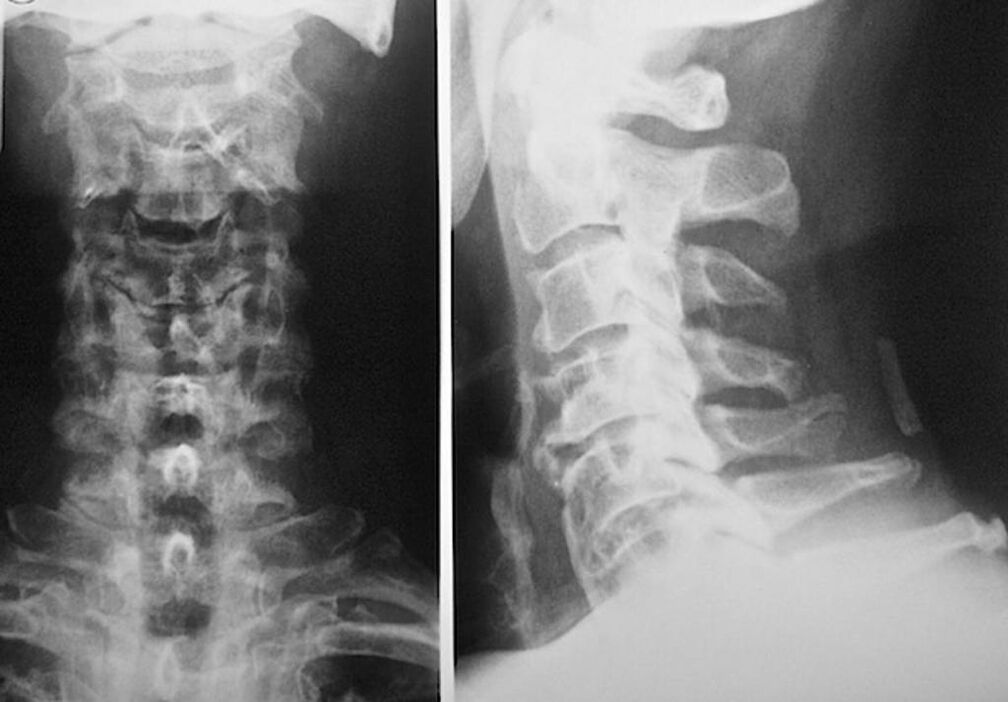

The following research methods are used to diagnose and accurately assess the condition of intervertebral discs:

- Radiography.

- CT scanner.

- Magnetic tomography.

- Ultrasound scan of the blood vessels of the neck.

Each of them is completely safe for health and does not carry any danger of overexposure. The diagnosis of osteochondrosis of the cervical vertebrae, whose treatment will be carried out for the rest of his life, can be made after a simple visual examination. Any orthopedist can do this easily. The exception is the first stage of the disease, when no visible pathologies of the cervical region are observed.